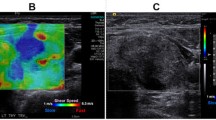

(left) Side-view schematic of the Cytophone. Near-infrared laser pulses (1064 nm, 100–300 µJ) were delivered through the skin of subjects. The photoacoustic emissions from CTCs and red blood cells were detected with cylindrically focused ultrasound transducers and separated based on their waveform. (right) a Photograph of setup with the subject’s arm and Cytophone apparatus; b Pulse echo cross sectional ultrasound image of the cubital vein; PA signal amplitude vs. time before (c) and after (d) one hour laser exposure; spikes indicate CTC detection events above a background threshold. Modified from [16]. (Color figure online)